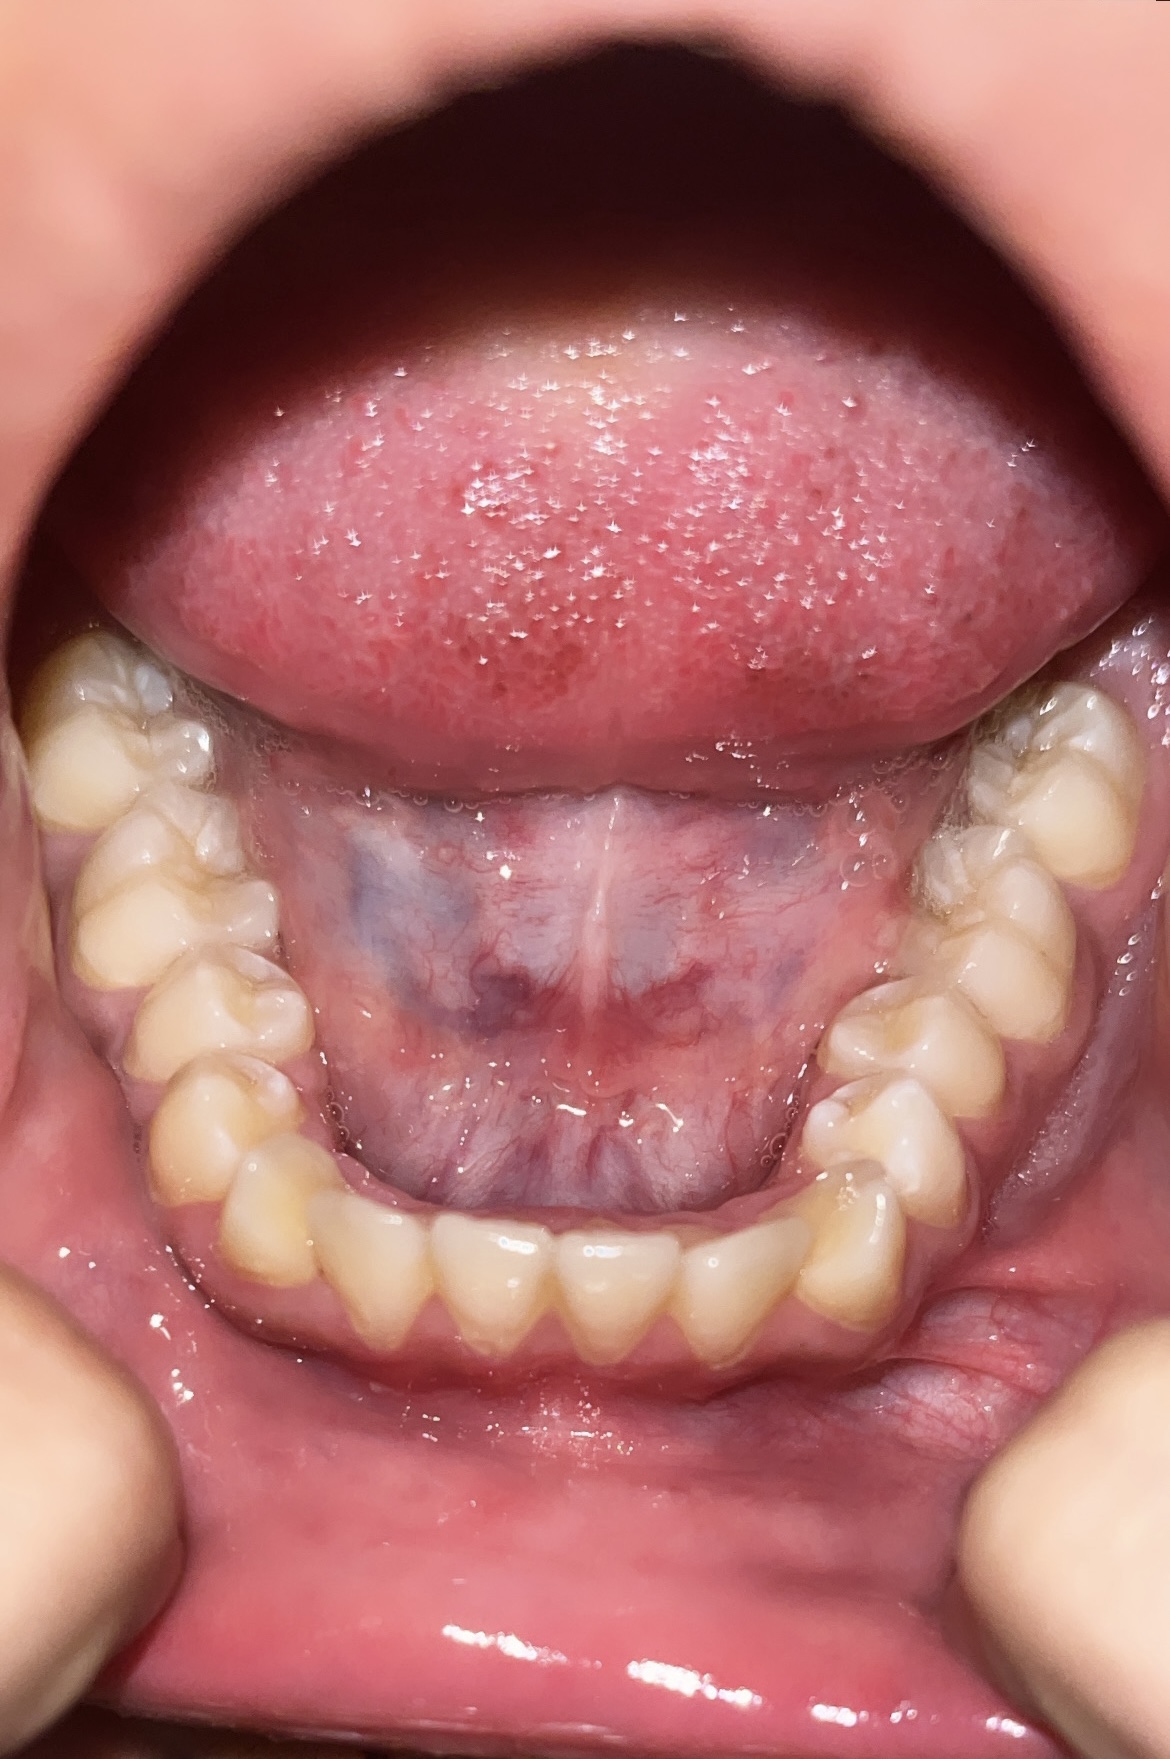

My palate and teeth are lowest tier

My incisors face inwards and outwards and canines also aren’t straight

Should i get palate expansion?

Or braces? I want braces which pull/push my teeth outwards

And can braces pull my teeth outwards or braces can only push them inside.